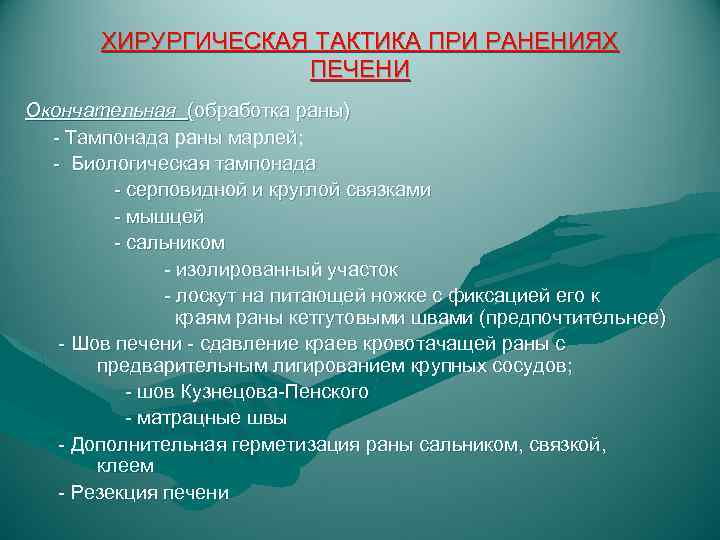

ХИРУРГИЧЕСКАЯ ТАКТИКА ПРИ РАНЕНИЯХ ПЕЧЕНИ Окончательная (обработка раны) - Тампонада раны марлей; - Биологическая тампонада - серповидной и круглой связками - мышцей - сальником - изолированный участок - лоскут на питающей ножке с фиксацией его к краям раны кетгутовыми швами (предпочтительнее) - Шов печени - сдавление краев кровотачащей раны с предварительным лигированием крупных сосудов; - шов Кузнецова-Пенского - матрацные швы - Дополнительная герметизация раны сальником, связкой, клеем - Резекция печени

ХИРУРГИЧЕСКАЯ ТАКТИКА ПРИ РАНЕНИЯХ ПЕЧЕНИ Окончательная (обработка раны) - Тампонада раны марлей; - Биологическая тампонада - серповидной и круглой связками - мышцей - сальником - изолированный участок - лоскут на питающей ножке с фиксацией его к краям раны кетгутовыми швами (предпочтительнее) - Шов печени - сдавление краев кровотачащей раны с предварительным лигированием крупных сосудов; - шов Кузнецова-Пенского - матрацные швы - Дополнительная герметизация раны сальником, связкой, клеем - Резекция печени